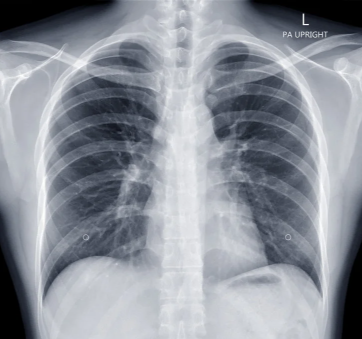

การเตรียมตัวก่อนการเอ็กซเรย์ โดยปกติแล้วสามารถรับประทานอาหารได้ตามปกติ ยกเว้นกรณีที่ผู้เข้ารับการตรวจบางราย จำเป็นต้องใช้สารเคมีในการตรวจ ควรงดการทานอาหารและยา และไม่ควรนำเครื่องประดับหรือโลหะ ติดตัวเข้าไป นอกจากนี้หากผู้ตรวจกำลังตั้งครรภ์ควรรีบบอกแพทย์ทันทีเพื่อเลื่อนการตรวจออกไปก่อน

ขั้นตอนการเอ็กซเรย์ ผู้เข้ารับการตรวจอาจต้องเปลี่ยนเสื้อผ้าตามที่โรงพยาบาลกำหนดไว้เมื่อเข้าสู่การเอ็กซเรย์ให้จัดท่าทางของร่างกายตามคำสั่งของแพทย์ผู้เชี่ยวชาญ ผู้เข้ารับการตรวจจำเป็นต้องอยู่นิ่งที่สุดเท่าที่จะเป็นไปได้ เพื่อให้ได้ภาพที่ชัดเจนที่สุด นอกจากนี้ผู้เข้า รับการตรวจบางรายอาจจำเป็นต้องใช้สารเคมีช่วยในการตรวจด้วย หลังจากที่เครื่องทำการเอ็กซเรย์เสร็จสิ้น แพทย์จะนำผลที่ได้ไป วินิจฉัยต่อไป

หลังการทำเอ็กซเรย์ ผู้เข้ารับการตรวจสามารถกลับบ้านหรือรอฟังผลได้เลย ทั้งนี้ขึ้นอยู่กับแพทย์ผู้เชี่ยวชาญส่วนผู้ที่จำเป็นต้องใช้สารทึบรังสี ในการตรวจนั้นไม่ต้องกังวลเกี่ยวกับผลกระทบ เพราะสารที่ใช้มีปริมาณรังสีที่น้อยมาก อย่างไรก็ตามอาจมีผลกระทบเกิดขึ้นกับร่างกายได้ เช่น ตาพร่ามัว อุจจาระมีสีซีด หรือมีผื่นขึ้น เป็นต้น ทั้งนี้หากพบอาการผิดปกติสามารถเข้ารับคำแนะนำจากแพทย์ได้